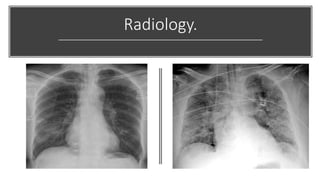

Radiology.